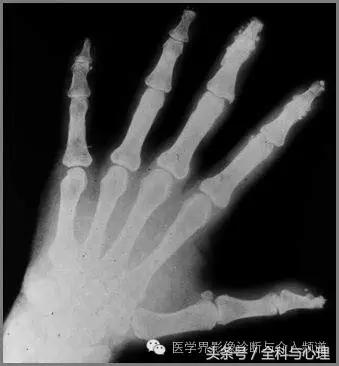

2、 与硬皮病相关的手部局限性钙质沉积

手部皮肤或皮下组织,多发的,边界清晰的,点状、片状的钙化灶,与硬皮病相关。

软组织钙化与骨化,软组织钙化和骨质增生 硬皮病

软组织钙化与骨化,软组织钙化和骨质增生

硬皮病